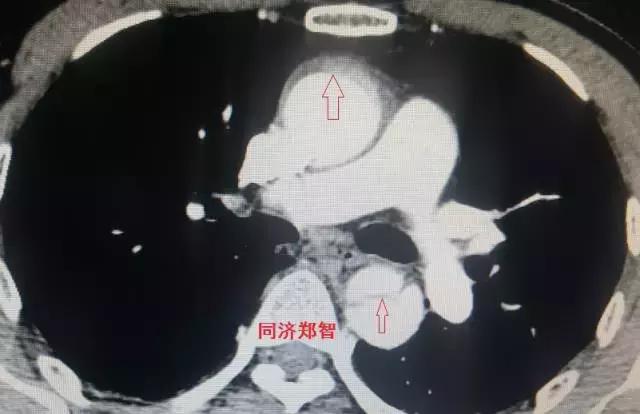

病例三

胸部平扫CT提示胸降动脉增宽(红色星形标记),CTA证实B型主动脉夹层伴降主动脉夹层动脉瘤形成。